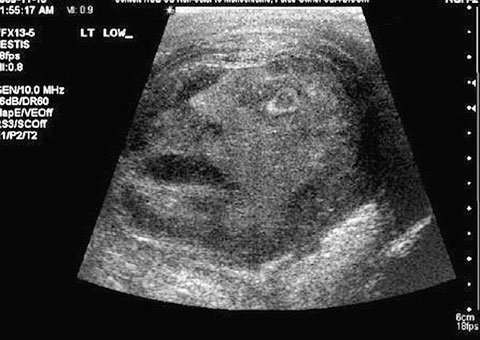

Default Phát hiện khuôn mặt quỷ trong khối u tinh hoàn

Các bác sĩ đã hết sức sửng sốt khi phát hiện một khuôn mặt quỷ qua màn hình khi siêu âm một khối u tinh hoàn.

Một người đàn ông 45 tuổi đã đi khám sau khi cảm thấy đau tinh hoàn. Trong quá trình siêu âm, các bác sĩ phụ trách đã phải giật mình khi thấy một gương mặt quỷ trên màn hình, ngay trong khối u tinh hoàn của bệnh nhân này. Tiến sĩ Greg Roberts và Tiến sĩ Naji Touma đến từ Trường đại học Queen (ở Ontario, Canada) đã gửi hình ảnh kinh ngạc này cho một tạp chí sức khỏe liên quan đến tiết niệu. Trong bức ảnh là một khuôn mặt ma quái với chiếc mồm há rộng, mắt mở to nhìn chằm chằm lên màn hình, vẻ sợ hãi.

Khuôn mặt quỷ qua màn hình khi siêu âm khối u tinh hoàn (Ảnh: Daily Mail)

Sau cuộc thảo luận xem liệu đây có phải là một dấu hiệu từ một vị thần hay thiên chúa nào không, các bác sĩ đã kết luận, đó chỉ là một trường hợp xảy ra ngẫu nhiên và hy hữu. Các chỉ số siêu âm cho thấy, bệnh nhân này bị viêm tinh hoàn nặng. Các bác sĩ cũng đo được một lượng hormone cao bất thường, dấu hiệu cho thấy bệnh nhân này đang trong quá trình chuyển bệnh ung thư. Bệnh nhân nam này sau đó đã được cắt bỏ khối u trong tinh hoàn.

Ung thư tinh hoàn thường xuất hiện ở nam giới trong độ tuổi từ 15 đến 55. Ở Anh, mỗi năm, người ta ước tính rằng cứ 100.000 người thì có từ 3 đến 6 trường hợp phát hiện mới bị ung thư tinh hoàn.